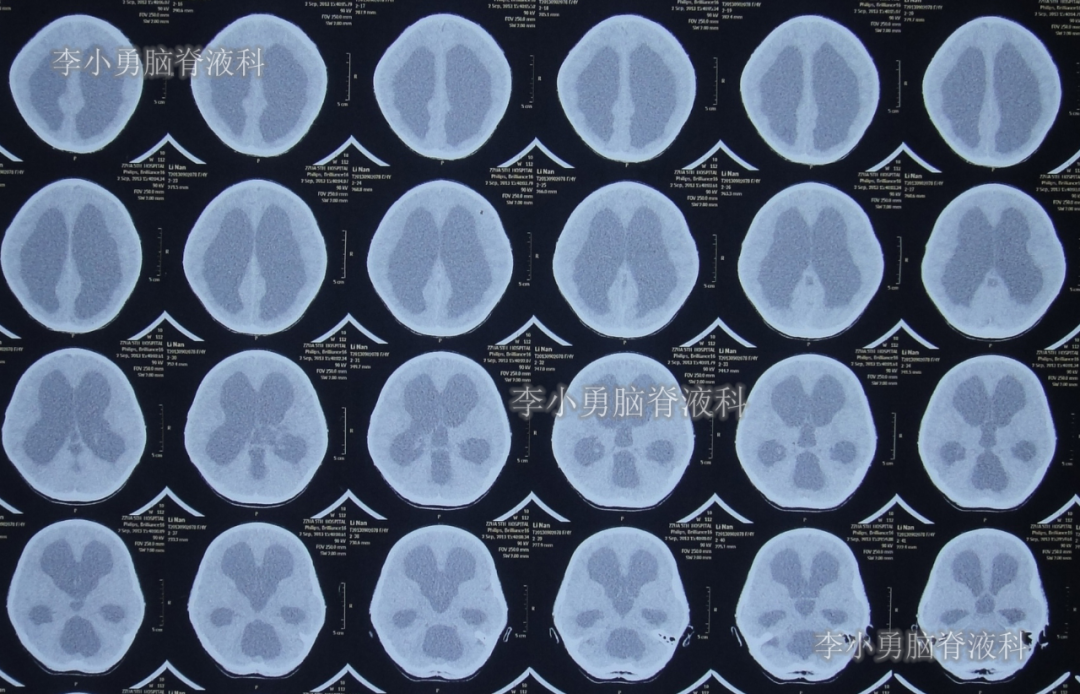

数天之后即在2013年9月2日,为治疗脑积水,患儿至河南省郑州市某三甲医院神经外科就诊,当日头颅CT示严重脑积水并第四脑室扩张严重(图-1);当天收入院。在住院后次日即2013年9月3日,进行了右侧额角脑室腹腔分流术。

图-1:2013年9月2 日头颅CT